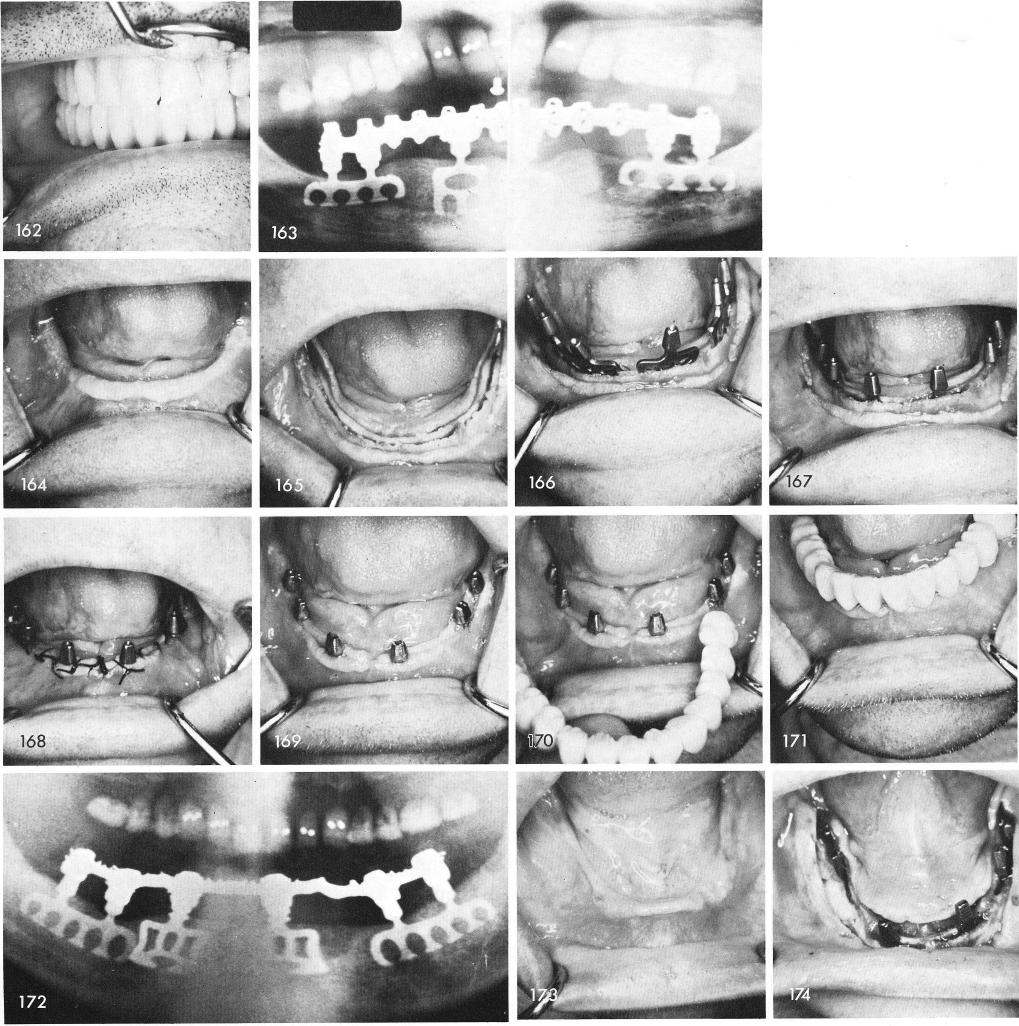

When the ridge is high and wide, fig. 164, the making of the grooves becomes less difficult, fig. 165. The blades can be tapped into position with a little more authority, figs. 166, 167, and the tissues are then sutured, fig. 168. Within several weeks healing is almost completed, fig. 169, and the bridgework is cemented with a hard cement, figs. 170, 171. Final x-ray, fig. 172. Sometimes there exists a labial overhang of bone, fig. 173, which should be removed to lessen the chances of perforation of the underlying labial plate of bone when the groove is made and the implants are set into them, fig. 174. The healed tissues, fig. 175, readily accept the full arch fixed restoration, figs. 176, 177, 178, 179. Final x-ray, fig. 180.

1 High and wide mandibular ridges